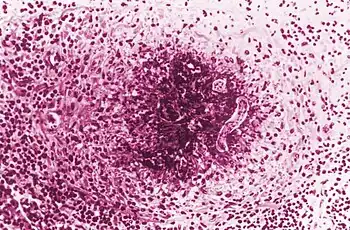

Finding Toxocara larvae within a patient is the only definitive diagnosis for toxocariasis; however, biopsies to look for second stage larvae in humans are generally not very effective.[10] PCR, ELISA, and serological testing are more commonly used to diagnose Toxocara infection.[10] Serological tests are dependent on the number of larvae within the patient, and are unfortunately not very specific.[10] ELISAs are much more reliable and currently have a 78% sensitivity and a 90% specificity.[27] A 2007 study announced an ELISA specific to Toxocara canis, which will minimize false positives from cross reactions with similar roundworms and will help distinguish if a patient is infected with T. canis or T. cati.[28] OLM is often diagnosed after a clinical examination.[27] Granulomas can be found throughout the body and can be visualized using ultrasound, MRI, and CT technologies.[10]

Parasitic loads as high as 300 larvae in a single gram of liver have been noted in humans.[10] The "excretory–secretory antigens of larvae ... released from their outer epicuticle coat [and] ... readily sloughed off when bound by specific antibodies" incite the host's immune response.[5] The tipping point between development of VLM and OLM is believed to be between 100 and 200 larvae.[10] The lighter infection in OLM is believed to stimulate a lower immune response and allow for migration of a larva into the eye. Larvae are thought to enter the eye through the optic nerve, central retinal artery, short posterior ciliary arteries, soft tissues, or cerebrospinal fluid.[10][13] Ocular granulomas that form around a larva typically are peripheral in the retina or optic disc.[13]